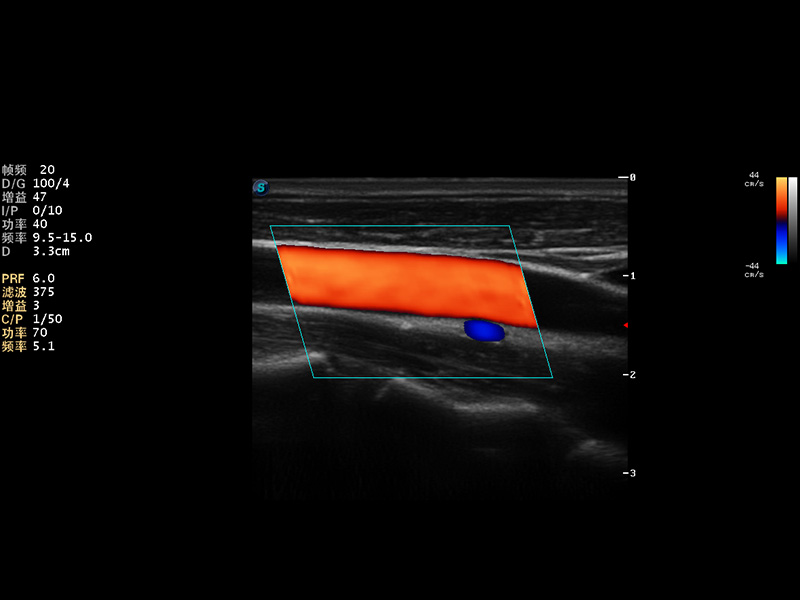

S9便携式彩色多普勒超声诊断仪是美狮贵宾会官网研发的高端便携彩超设备,外观设计新颖、产品性能卓越。S9在便携超声领域采用了突破传统的触摸屏交互设计,并以先进的软件硬件技术和设计理念,为您带来清晰的图像质量、稳定的工作性能和便捷的操作体验。

AutoC智能血流追踪